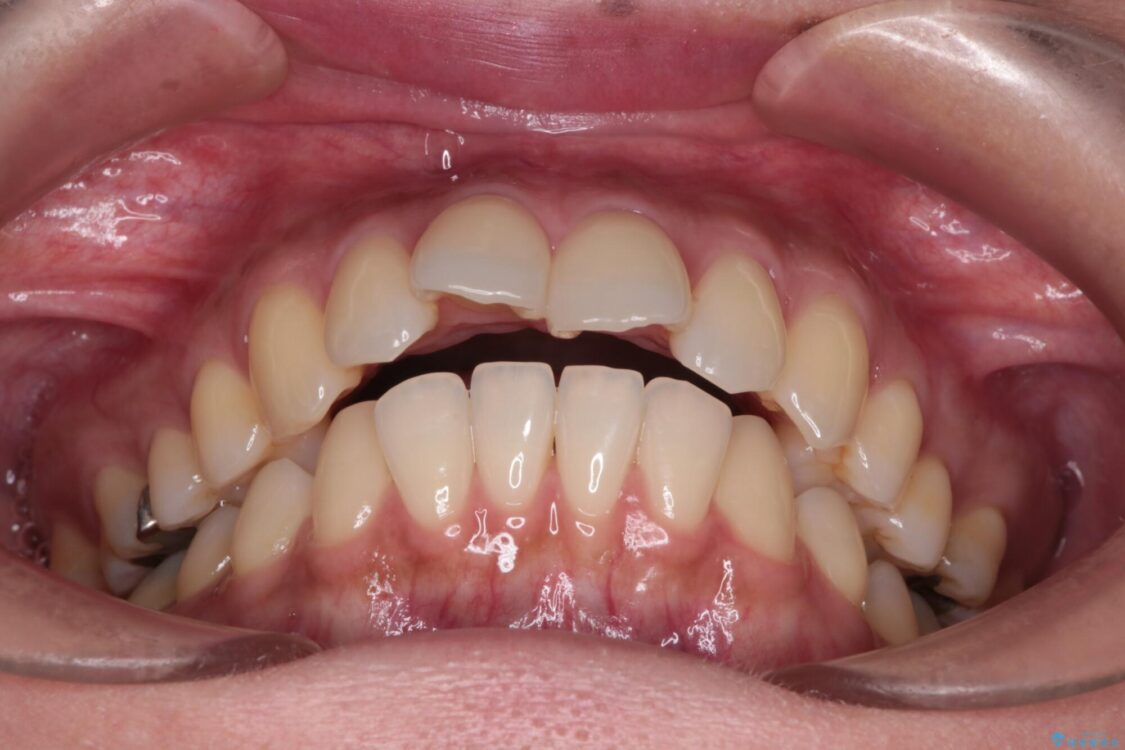

上の前歯の突出感を気にして来院された患者様です。

治療前

• 上顎前歯の突出を軽減 インビザラインによる抜歯矯正 治療前画像